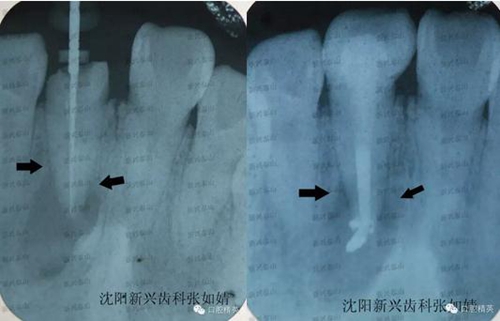

戴牙后拍了一張X線片,根管治療一個月了,我想看下他牙根炎癥是否有所好轉(zhuǎn)。

真實的蛻變----熱牙膠根管充填之后的牙冠修復真實的蛻變----熱牙膠根管充填之后的牙冠修復,左圖為治療時確定牙根長度是否準確時拍的X線片,右圖為戴牙之后X線影像,右圖牙齒有些拉長了。

兩圖對比,注意箭頭指向處距根尖的位置,治療后炎癥區(qū)域,即根尖的大面積陰影,有好轉(zhuǎn)的跡象,陰影的邊緣開始向根尖縮聚。由于炎癥太重,根尖此處的病灶要慢慢吸收,是一個過程,治療一個月時間,已好轉(zhuǎn)很多,長期追蹤這個患者的病情,定期復診,觀察病灶區(qū)域的變化,及時掌握牙齒情況。

從右圖顯而易見的,牙冠修復體的透光度和鄰牙非常接近,沒有形成低密度阻射的影像。